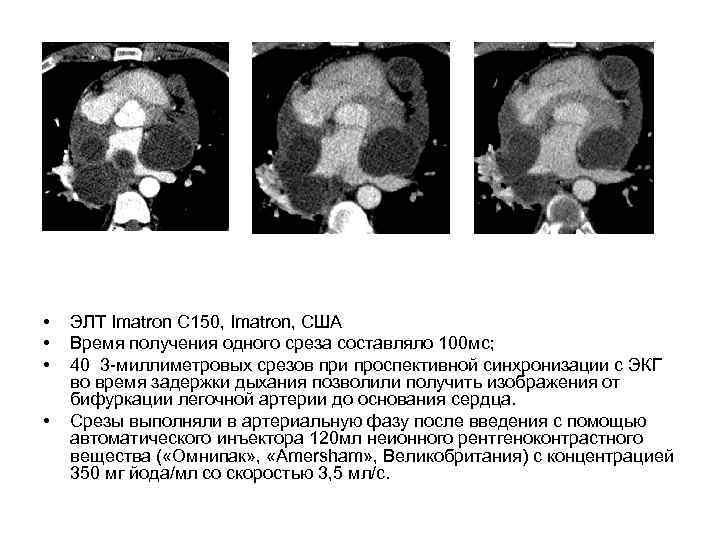

• • ЭЛТ Imatron C 150, Imatron, США Время получения одного среза составляло 100 мс; 40 3 -миллиметровых срезов при проспективной синхронизации с ЭКГ во время задержки дыхания позволили получить изображения от бифуркации легочной артерии до основания сердца. Срезы выполняли в артериальную фазу после введения с помощью автоматического инъектора 120 мл неионного рентгеноконтрастного вещества ( «Омнипак» , «Amersham» , Великобритания) с концентрацией 350 мг йода/мл со скоростью 3, 5 мл/с.